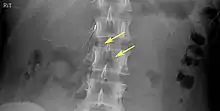

IVC filters are placed endovascularly, meaning that they are inserted via the blood vessels. Historically, IVC filters were placed surgically, but with modern filters that can be compressed into much thinner catheters, access to the venous system can be obtained via the femoral vein (the large vein in the groin), the internal jugular vein (the large vein in the neck) or the arm veins with one design. Choice of route depends mainly on the number and location of any blood clot within the venous system. To place the filter, a catheter is guided into the IVC using fluoroscopic guidance, then the filter is pushed through the catheter and deployed into the desired location, usually just below the junction of the IVC and the lowest renal vein.[43]

Review of prior cross-sectional imaging or a venogram of the IVC is performed before deploying the filter to assess for potential anatomic variations, thrombi within the IVC, or areas of stenoses, as well as to estimate the diameter of the IVC. Rarely, ultrasound-guided placement is preferred in the setting of contrast allergy, chronic kidney disease, and when patient immobility is desired. The size of the IVC may affect which filter is deployed, as some (such as the Birds Nest) are approved to accommodate larger cavae. There are situations where the filter is placed above the renal veins (e.g. pregnant patients or women of childbearing age, renal or gonadal vein thromboses, etc.). Also, if there is duplication of the IVC, the filter is placed above the confluence of the two IVCs [44] or a filter can be placed within each IVC.[45]